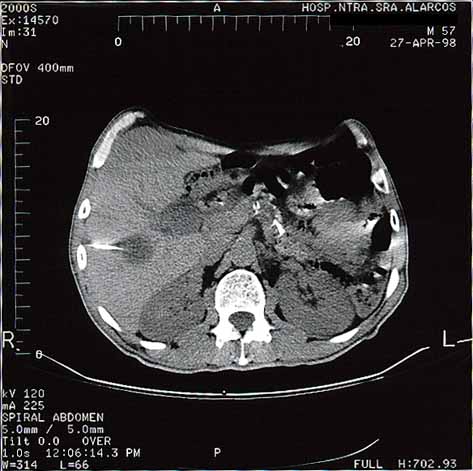

fig. 2

Figura 2. TAC Higado durante PAAF de hígado.